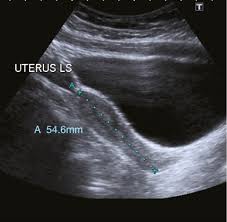

Your doctor might order this test to diagnose a condition, or to check the health of your baby. It allows your doctor to see your bladder, cervix, uterus, fallopian tubes, and ovaries. The sound waves create a picture on a video monitor. An ultrasound of the pelvis is typically used to look at the bladder, ovaries, uterus, cervix, and fallopian tubes (some of these are known as the female reproductive organs). Your doctor is easily able to view the uterus, cervix, vagina, fallopian tubes and ovaries during a pelvic ultrasound.

The ultrasound is a critical modality for the evaluation of the contents of the female pelvis. Your doctor is easily able to view the uterus, cervix, vagina, fallopian tubes and ovaries during a pelvic ultrasound. Transvaginal pelvic ultrasound protocol transvaginal ultrasound gives the best resolution and visualization of the female pelvic structures. The test can be done in two ways: An ultrasound of the pelvis is typically used to look at the bladder, ovaries, uterus, cervix, and fallopian tubes (some of these are known as the female reproductive organs). Normal pelvic ultrasound nazari l,. Us uses no ionizing radiation (which can cause cancer and birth defects in fetus) ©aium goals&objectives • be familiar with how us images are. Female pelvis ultrasound protocol the patient should be scanned either trans abdominally (ta) with a full bladder or trans vaginally (tv). Female pelvis ultrasound protocol reviewed by: The approach your doctor recommends for your ultrasound depends on the reason for your test and whether you are a man or a woman. It allows your doctor to see your bladder, cervix, uterus, fallopian tubes, and ovaries. A pelvic ultrasound is a test that uses sound waves to make a picture of the inside of the lower belly (pelvis). When is a pelvic ultrasound recommended?